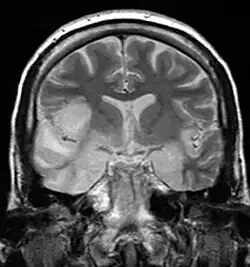

In der Magnetresonanztomographie, die für die Diagnose meist richtungsweisend ist, sind temporal und basal enzephalitische Herde mit dem Einsetzen zentralnervöser Symptome erkennbar. Die Computertomographie des Schädels weist in den ersten Tagen der Symptomatik regelhaft noch keine Auffälligkeiten auf. Auch Ableitungen im EEG zeigen erst nach fünf bis elf Tagen pathologische Allgemeinveränderungen im Sinne einer Enzephalitis, typischerweise mit epileptiformen Mustern über den frontalen und temporalen Regionen.